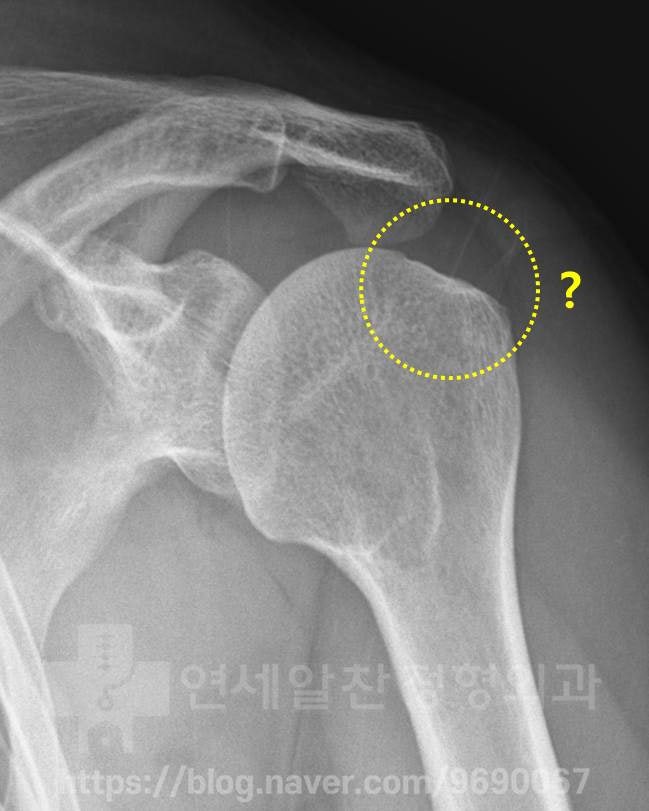

X-ray 상에서는 정상적인 소견이 관찰됩니다.

MRI 상에서 극상근 부위에 정상적으로는 검게 보여야 할 인대가 하얗게 보이면서 심한 염증소견이 보이고 있습니다. 이것을 심한 건증(인대가 약해진것)으로 판단하고 이것에 대한 봉합술을 권고 받은 것으로 보입니다. 하지만 자세히 보면 MRI 상에서 극상근 안에 조그만 까만 점이 보이는 것이 보이며 미세한 석회로 생각됩니다. 그래서 초음파 검사를 통해 다시 한번 확인해 보기로 하였습니다.